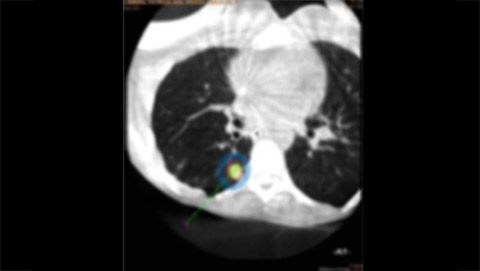

XperGuide Ablation enables real-time needle guidance in the angio suite. Virtual needle paths are created by overlaying previously acquired MR or CT datasets with XperCT data to enable optimal planning of one or multiple needles for full tumor coverage. XperGuide Ablation supports all ablation techniques (such as RF, microwave and cryo-ablation) by displaying the isotherm of the ablation needles.